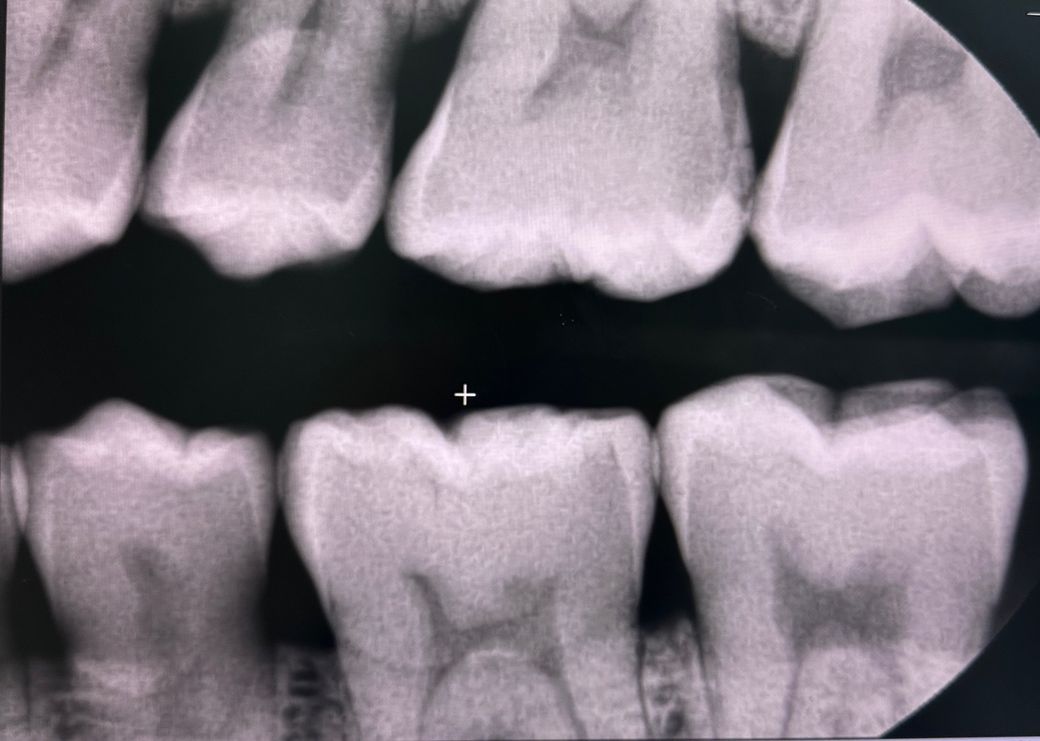

약 2주전 찬바람, 찬물이 닿으면 시려서 치과를 방문하였고 엑스레이 2번 찍었는데 첫번째는 전체적인 엑스레이, 두번째 사진은 왼쪽 치아만 찍은 엑스레이입니다.

엑스레이 결과 염증은 없고, 왼쪽 위 뒤에서 첫번째, 두번째 치아 충치가 의심되지만 애매해서 정기검진때 확인해보자하여 알겠다하였으며, 후에 치경부 마모증으로 인한 시림이라고 레진을 받았습니다.